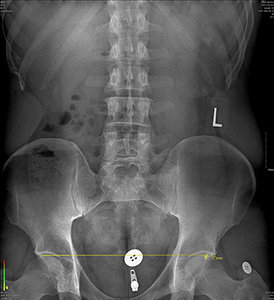

FIG 3 Standing X-ray with bilateral orthotic support and 6 mm heel lift on right.

No history of trauma was reported, but pain in the right knee and hip were only experienced upon running 10 miles or more.

There was an unremarkable orthopedic exam. Digital laser scan of the plantar vault revealed symmetrical lateral arch collapse. In addition, an apparent 14 mm reduction deficit was noted in the right femur upon X-ray.

The patient was fitted with custom three-arch foot orthotics and lumbopelvic X-rays were repeated. With the orthotics, the actual reduction deficit in the right femur was measured at 6 mm. A 6 mm heel lift was added on the right and follow-up X-ray revealed a zero-deficit femoral head height measurement.

With ancillary treatment for symptomatic relief and a slow progression in running mileage, the patient was returned to marathon training with full condition resolution.